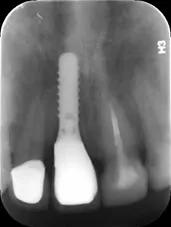

种植牙是将种植体(金属钛,可与人体结合)放入缺牙区的牙槽骨充当人工牙根,不依靠邻牙就能站稳脚跟。

种植牙形态美观、舒适、固位稳定,功能与天然牙近似,能高效地行使咀嚼功能,且无需磨损旁边的牙齿,对邻牙没有任何伤害。

无需活动牙类似的卡环或基托,没有异物感,寿命长,只要不是遇人不淑没种好,种上的牙齿至少能用30余年。

而且种植手术是一个较小的手术,类似拔牙手术,采用局部麻醉,手术只需要半小时左右即可完成,创伤小,术后2小时即可进食。缺点是种植牙的成本比较高、对口腔医生的技术要求也较高,治疗费用相对比较高。